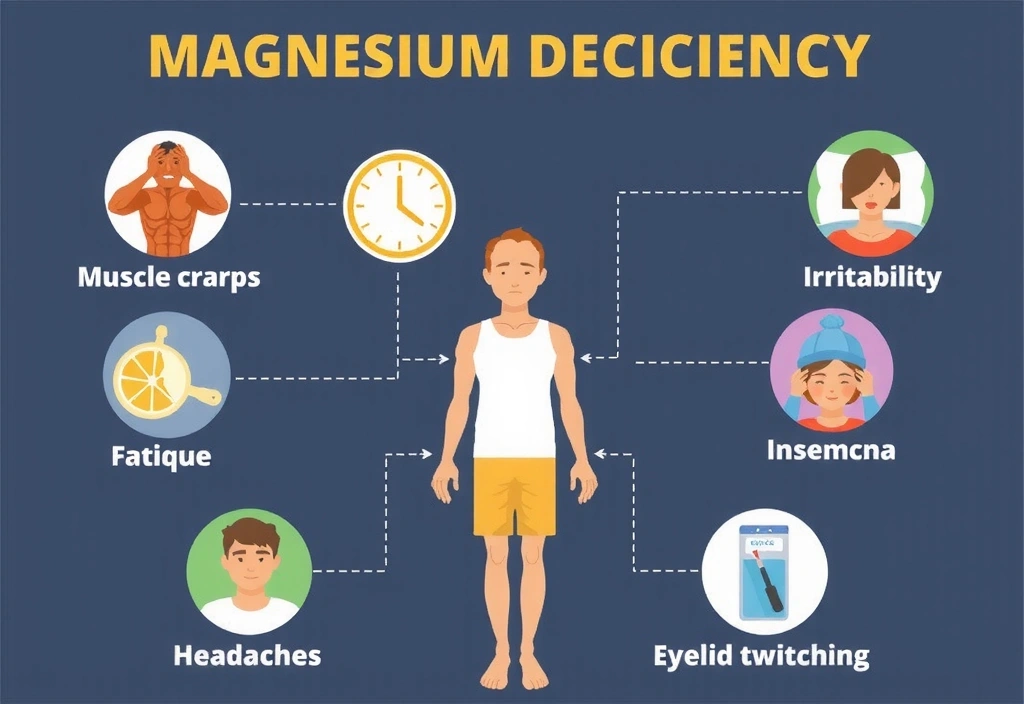

Objawy Niedoboru i Kiedy Suplementować Magnez

Niedobór magnezu, choć często bagatelizowany, jest powszechny w dzisiejszym społeczeństwie i może objawiać się szeregiem nieprzyjemnych symptomów. Do najbardziej typowych należą skurcze mięśni, szczególnie łydek, uczucie chronicznego zmęczenia i znużenia, a także zwiększona drażliwość i problemy z koncentracją. Osoby z niedoborem magnezu często doświadczają bezsenności lub trudności z zasypianiem, bólów głowy, a nawet drgania powiek.